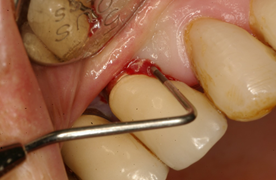

Como en toda patología, el correcto diagnóstico es fundamental para establecer un adecuado tratamiento. Los parámetros a tener en cuenta son: el Sangrado al Sondaje y/o Supuración (SS) (Fig. 5) y Profundidad al Sondaje (Fig. 6) aumentada con respecto al examen inicial y control radiográfico. Otros métodos de diagnóstico aportan poca información, son más costosos y complejos de realizar.

La presencia de SS en una exploración delicada, con una presión no mayor a 0.25N es un parámetro muy útil para el diagnóstico tanto de la mucositis como de la peri-implantitis. Numerosos estudios han encontrado una relación directa entre el SS y la pérdida de inserción alrededor del implante. Un estudio prospectivo cuyo objetivo fue monitorear las condiciones de la mucosa peri-implantar durante la terapia periodontal de apoyo, reveló que el sangrado en un mismo sitio, en más de la mitad de las visitas de mantenimiento, durante un período de 2 años se relaciona con el progreso de la enfermedad6.